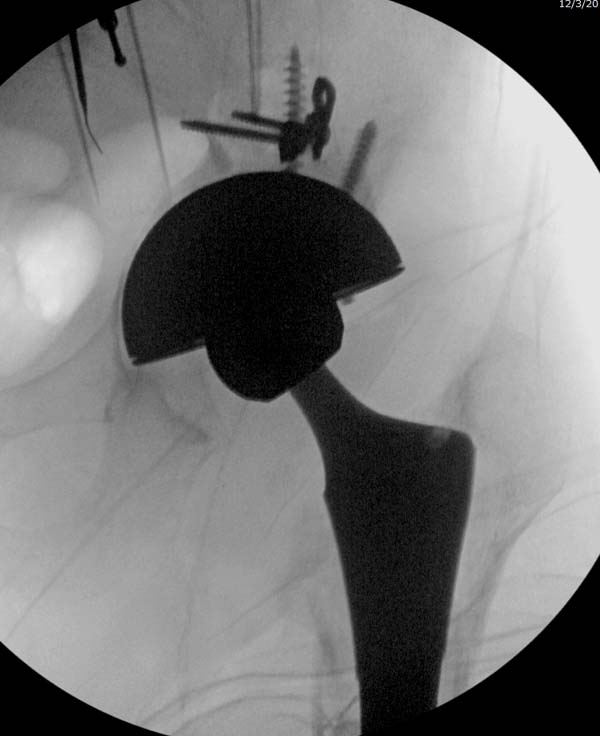

Теперь по серьезному. Учитывая качество кости и низкий гемоглобин,

периодический гемодиализ и воодушевленный результатом выступлении

Челнокова, вместо пластины решил попробовать гвоздь. Но жесткие FDА

условии не позволяют воспользоваться дивайсом до получения разрешения на

Гвоздь из ретроградного гвоздя DePuy в 15 мм получился немного тоньше,

чем у Российских коллег.

А так вроде первый американский опыт прошел удачно. У больного низкий

гемоглобин, который подправили во время операции переливанием крови.

надеюсь, контрагированные мышцы сохранит длину конечности. Контрольный

снимок показал устойчивую фиксацию.